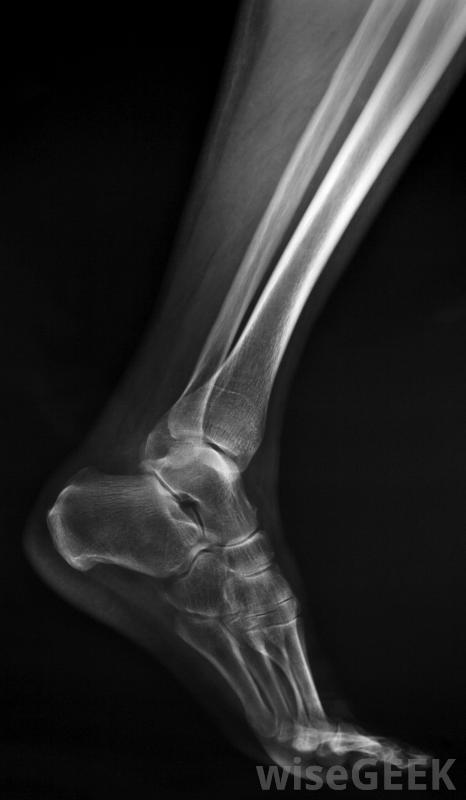

如果没有X光片,不可能知道与撕脱骨折相关的骨骼损伤程度。这种损伤听起来非常严重,但在许多情况下,治疗撕脱性骨折的黄金标准是让人们休息,根据需要使用糖霜来消肿,可能还需要开一些消炎药来帮助减轻炎症。休息时间可以持续两到六周,这取决于损伤的严重程度。通常情况下,这足以让骨骼重新附着并愈合一些医生计划在一个设定的时间点进行后续的x光检查,以确保再次附着成功。